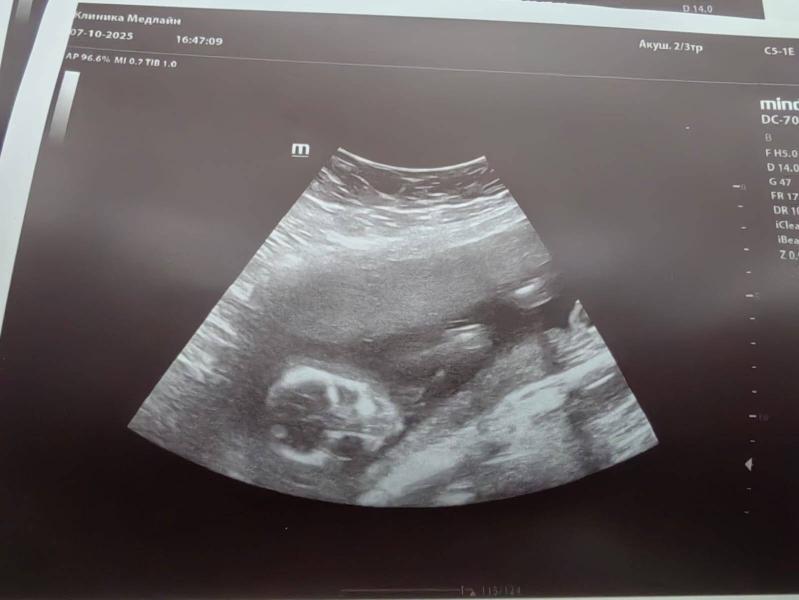

Первые фотки человечка🤗так и не узнали мы кто в "теремочке" живет, очень глубоко сидит и скромничает. Лежит, посасывает палец. Есть предположение что девочка, потому что отчетливого писюна не увидела, как это было у сына. Низкая плацентация сохраняется, перекрывает немного зев.

Девочка вероятнее всего на уз.